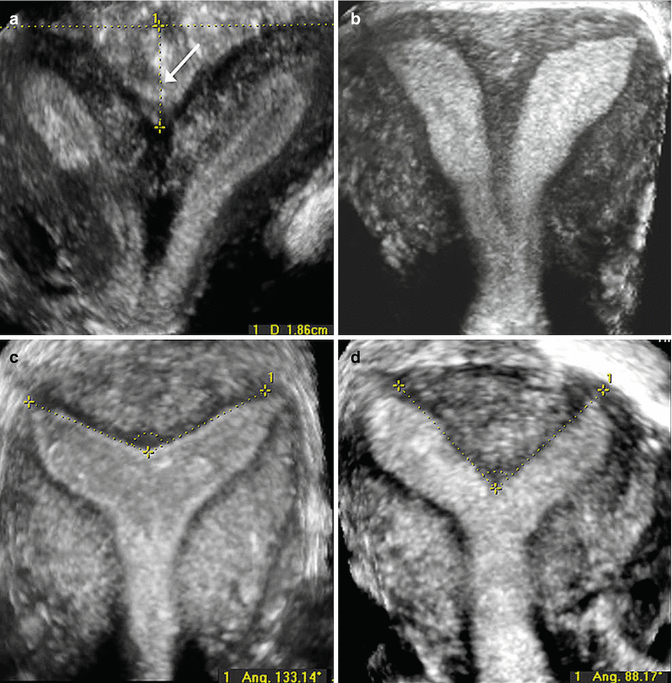

Three Dimensional Ultrasound Image Of A Didelphys Uterus Duplication Download Scientific Diagram